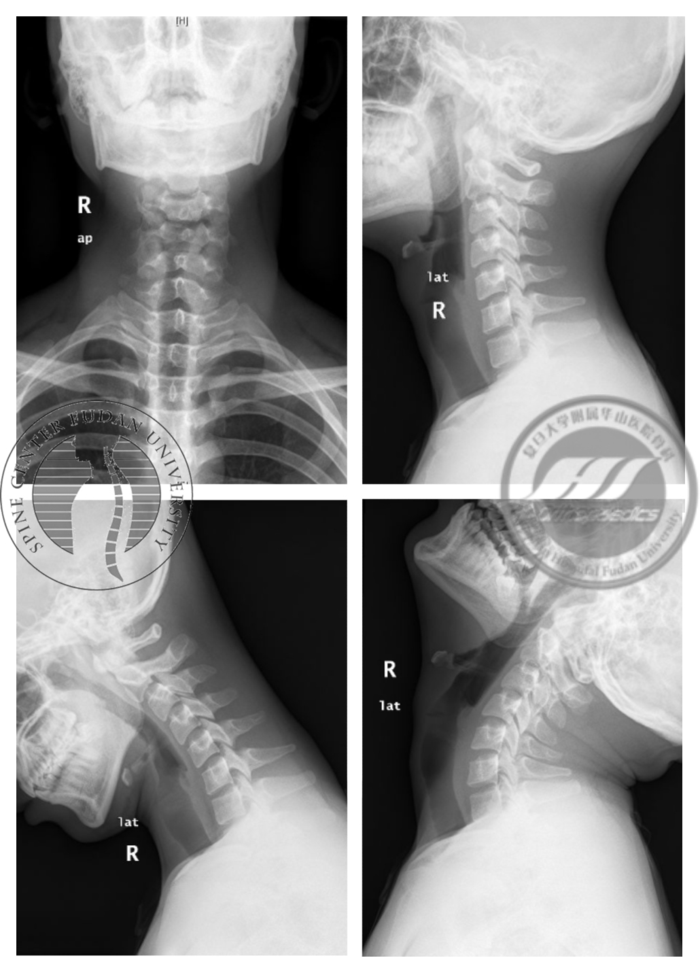

图5 颈椎正侧位及过屈过伸位X线,显示患者颈椎生理曲度变直,活动度正常